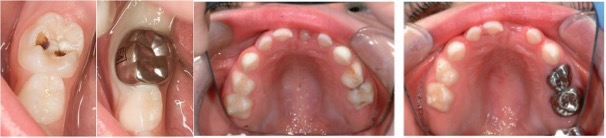

Chụp thép răng sữa (còn gọi là chụp thép tiền chế) là phương pháp phục hình nha khoa hiện đại, sử dụng mão răng giả làm từ hợp kim thép không gỉ để bảo vệ răng sữa bị sâu nặng, vỡ lớn hoặc sau khi điều trị tủy. Chụp thép giúp duy trì chức năng ăn nhai, bảo vệ mô răng còn lại và giữ chỗ cho răng vĩnh viễn mọc đúng vị trí.

Quy trình chụp thép răng sữa

Quy trình chụp thép tiền chế gồm các bước sau:

• Bước 1: Bác sĩ tiến hành kiểm tra tình trạng răng sữa của trẻ, xác định răng cần phục hồi bằng chụp thép.

• Bước 2: Làm sạch khu vực răng sâu hoặc tổn thương, loại bỏ vi khuẩn, mảng bám và thức ăn dư thừa. Nếu cần, sẽ thực hiện điều trị tủy trước khi tiến hành bọc chụp.

• Bước 3: Mài chỉnh thân răng để tạo khoảng trống phù hợp, đảm bảo chụp thép không gây cấn với các răng kế bên. Nếu cần, bác sĩ cũng có thể mài hạ thấp mặt răng để duy trì khớp cắn tự nhiên.

• Bước 4: Lựa chọn kích thước chụp thép phù hợp, sát khuẩn và làm khô bề mặt răng. Sau đó, sử dụng keo nha khoa để cố định chụp thép, đồng thời kiểm tra độ vừa vặn và ổn định.

• Bước 5: Kiểm tra lại khả năng ăn nhai và tính thẩm mỹ sau khi chụp thép. Bác sĩ sẽ hướng dẫn trẻ và phụ huynh cách chăm sóc, vệ sinh răng miệng đúng cách, đồng thời hẹn lịch tái khám định kỳ để theo dõi tình trạng răng.